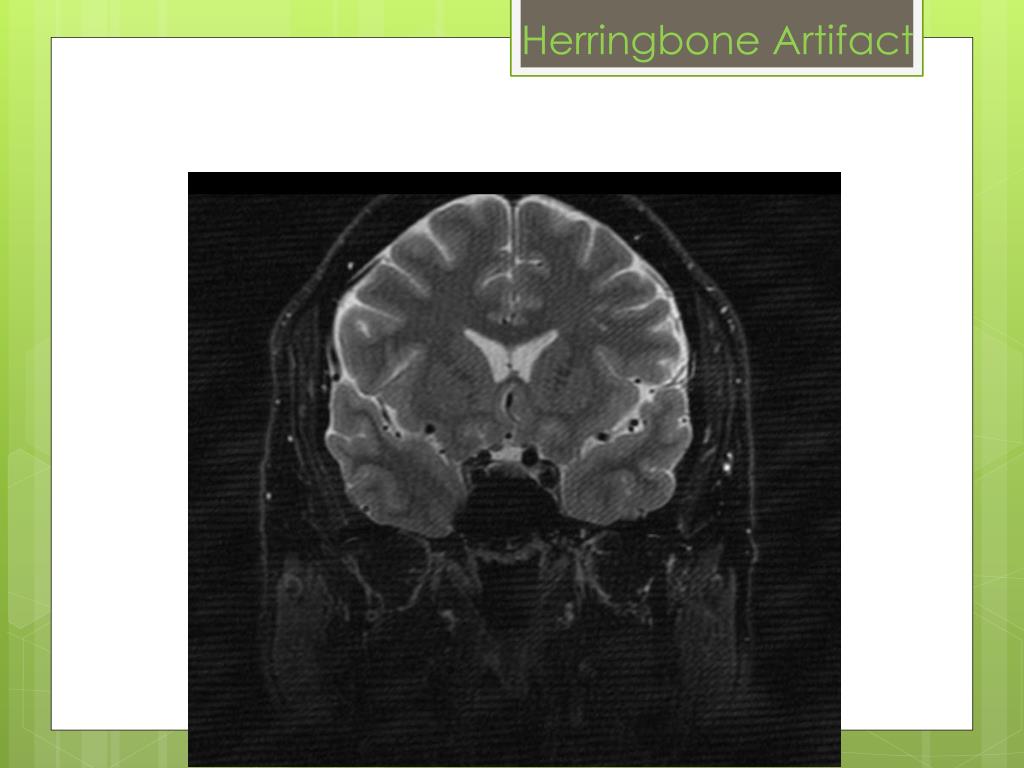

2. Spike (Herringbone) • Bad data point/noise spike in k-space • Either very high / low intensity compared w/ rest of image • Spike is convolved with all other image info during FT • Since each image pixel is a weighted sum of all individual points in k-space • Results in dark stripes overlaid on image • Occurs with high duty cycle gradients sequences • Loose connection/breakdown of connections in RF coil

5. Herringbone Artifact